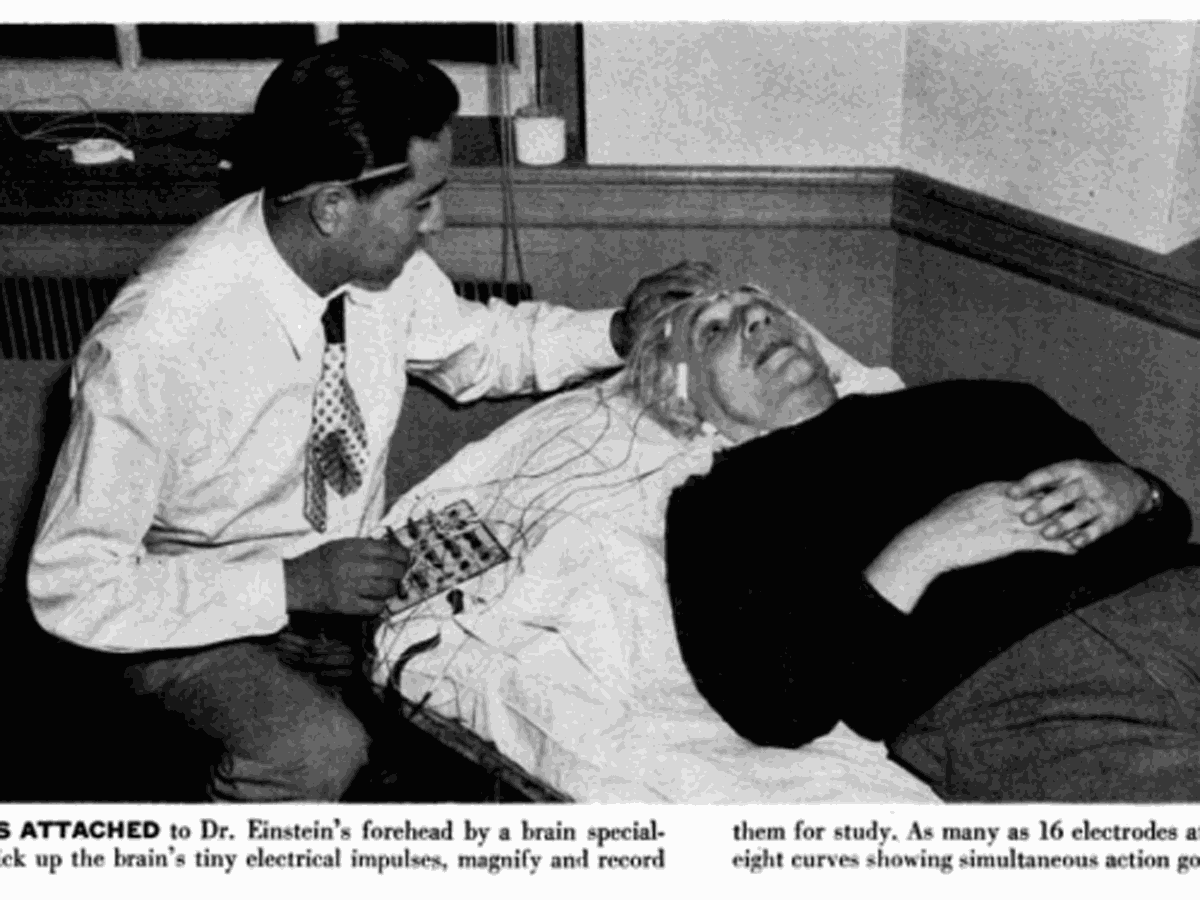

Https www alamy com a specimen of nobel physicist albert einsteins brain is seen in a glass slide at an exhibition at the wellcome collection in london march 27 2012 weve pickled it dessicated it drilled it mummified it chopped it and sliced it over centuries yet as the most complex entity in the known universe the human brain remains a mysterious fascination with samples of albert einsteins preserved brain on slides and specimens from other famous and infamous heads such as the english mathematician charles babbage and notorious mass murderer william burke an exhibition opening in london this week image377121679 html (Dateityp jpg)

Einsteins Brain High Resolution Stock Photography And Images Alamy